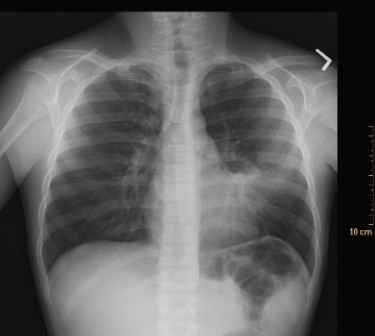

This image includes a classic radiographic finding. What is the name of this radiologic sign, and what is the most likely disease?